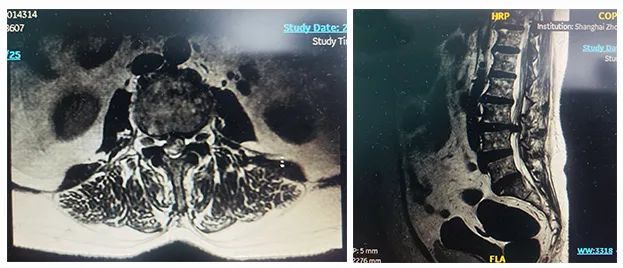

病例二

患者:女性,58歲

術(shù)式:腰骶椎椎體間融合術(shù)

患者一個月前因雙側(cè)下肢疼痛至醫(yī)院就診,診斷為腰椎間盤突出?;颊咦孕兄猎\所就診,予以推拿牽引術(shù),疼痛未明顯緩解,到醫(yī)院進一步治療。影像診斷:L3-4椎間盤突出,椎管變窄(中央型)。

術(shù)前影像